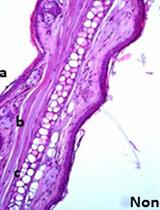

Cyst Detection in Toxoplasma gondii Infected Mice and Rats Brain